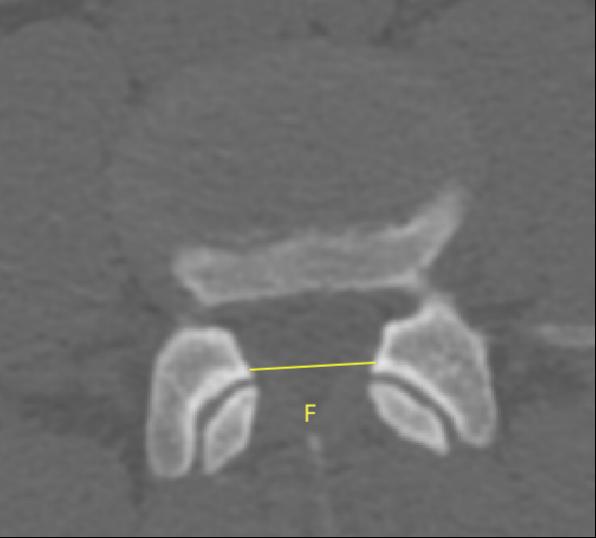

2、通过术前CT测量L4-5节段手术部位的(1)上位椎体后下角水平方向到关节突关节的距离(A);(2)纤维环后缘的中点水平方向到关节突关节的距离(B);(3)下位椎体后上角水平到关节突的距离(C);(4)上位椎体的椎弓下切迹与下位椎体椎弓上切迹连线的距离(D),图 6;(5)在手术节段的棘突矢状位CT层测量椎间隙高度(E),图 7;(6)在手术节段的关节突关节横截面CT层测量关节突间距离(F),图 8,再通过术中及术后CT判断患者椎间孔成型级别,将A-F测量数据与5级成型中的各级别成型进行相关性分析。

图 8 F的测量方式 |